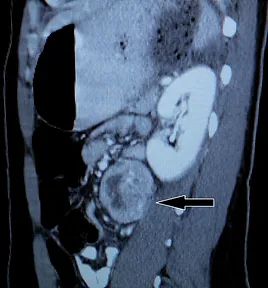

A hormone-secreting tumour that can occur in the adrenal glands. Phaeochromocytomas usually develop in the small glands on top of the kidneys (adrenal glands). They most commonly affect people between the ages of 20 and 50, but can occur at any age. Because of hormones secreted, symptoms include high blood pressure, sweating, rapid heartbeat and headache. Surgery to remove the tumour is usually required.